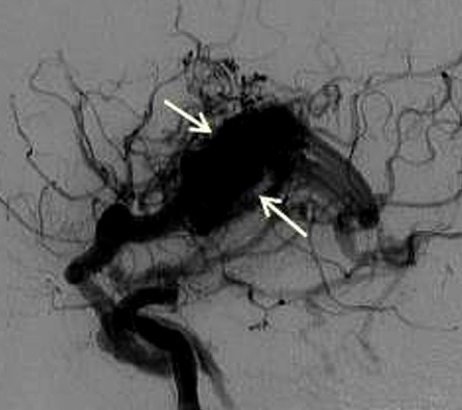

脑动静脉畸形(AVMs)是血管系统的缺陷,由异常血管缠结(nidus)组成,其中供血动脉在没有毛细血管床的介入下,直接连接到静脉引流网络。动脉将富含氧气的血液从心脏输送到身体其他组织和细胞,静脉将缺氧的血液送回肺部和心脏,毛细血管连接动脉和静脉。

4、血管内治疗:血管内栓塞治疗是手术切除或放射外科治疗前的合适辅助治疗办法,通过一次或数次栓塞治疗将畸形团变小、栓塞其中的伴发动脉瘤、高流量动静脉瘘等,为手术、放射外科治疗创造条件。该方法为微创介入方法,相对风险及并发症小于开颅手术,但单纯介入治愈率低。有约5%的患者可以通过单存血管内治疗完全治愈脑动静脉畸形。